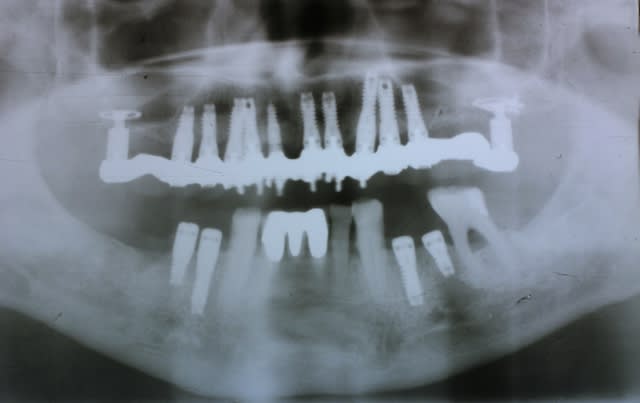

Pp vous remet bien le bonjour à tous et part en vacances après s'être bcp trop amusé ces temps-ci...

Parce que 6 en bas, ça te condamne à faire des extensions distales si tu veux un semblant de molaire

Et sur le long terme les extensions c est pas top

Et qd tu fais des prothèses "courtes" qui s arrêtent aux prémolaires, les patients se plaignent svt de ne pas avoir de molaires et donc de puissance masticatoire

Mais chaque praticien fait comme il veut, comme il le sent et comme il arrive à la faire passer à ses patients

Pour ma part ils sont tjs contents d avoir une bouche complète avec des molaires fixes et bien soutenues donc je n ai aucune raison de faire autrement...et stt pas de raison économique qui me pousseraient à leur proposer 6 implants sans molaires

Certes je "perds" sans doute des patients en proposant un nombre d implants plus élévés que des confrères mais je veux juste une grande sécurité et leur confort donc on ne déroge pas à la règle

Sérieusement, plus de 10 par arcades, c'est bcp.

Dans ton cas, j'aime pas les kissing implants, zolis nom pour une belle gaffe, sans rancune.